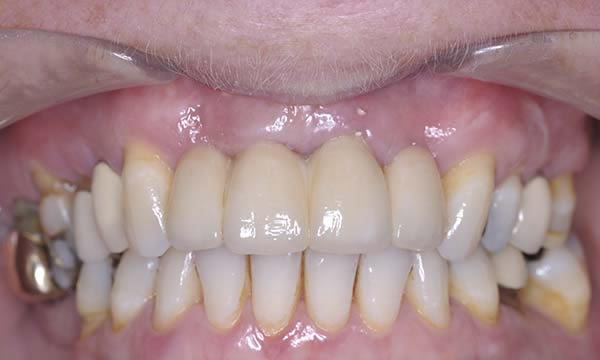

Case H

This case is a collaboration between ourselves and a specialist periodontist based in the referring practice. A case of patience, where a patient wanted to be rid of his un-retentive denture replacing the UL1 while stabilising his periodontal disease with improved home care and treatment from a specialist periodontist.

After approximately 12 months of periodontal therapy, the patient was deemed stable enough by the specialist periodontist to undergo implant treatment. An Astra EV implant was placed and a well shade matched zirconia crown was luted to an Atlantis abutment. Digital SLR pictures were used to provide the lab technician with appearance detail of the neighbouring dentition, to allow the technicians at Smile Dental Laboratory to introduce 'accents' and a realistic and seamless look to the final zirconia prosthesis.

After Treatment